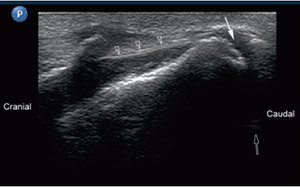

تصویر سونوگرافی سوزن در محل گانگلیون ایمپار: